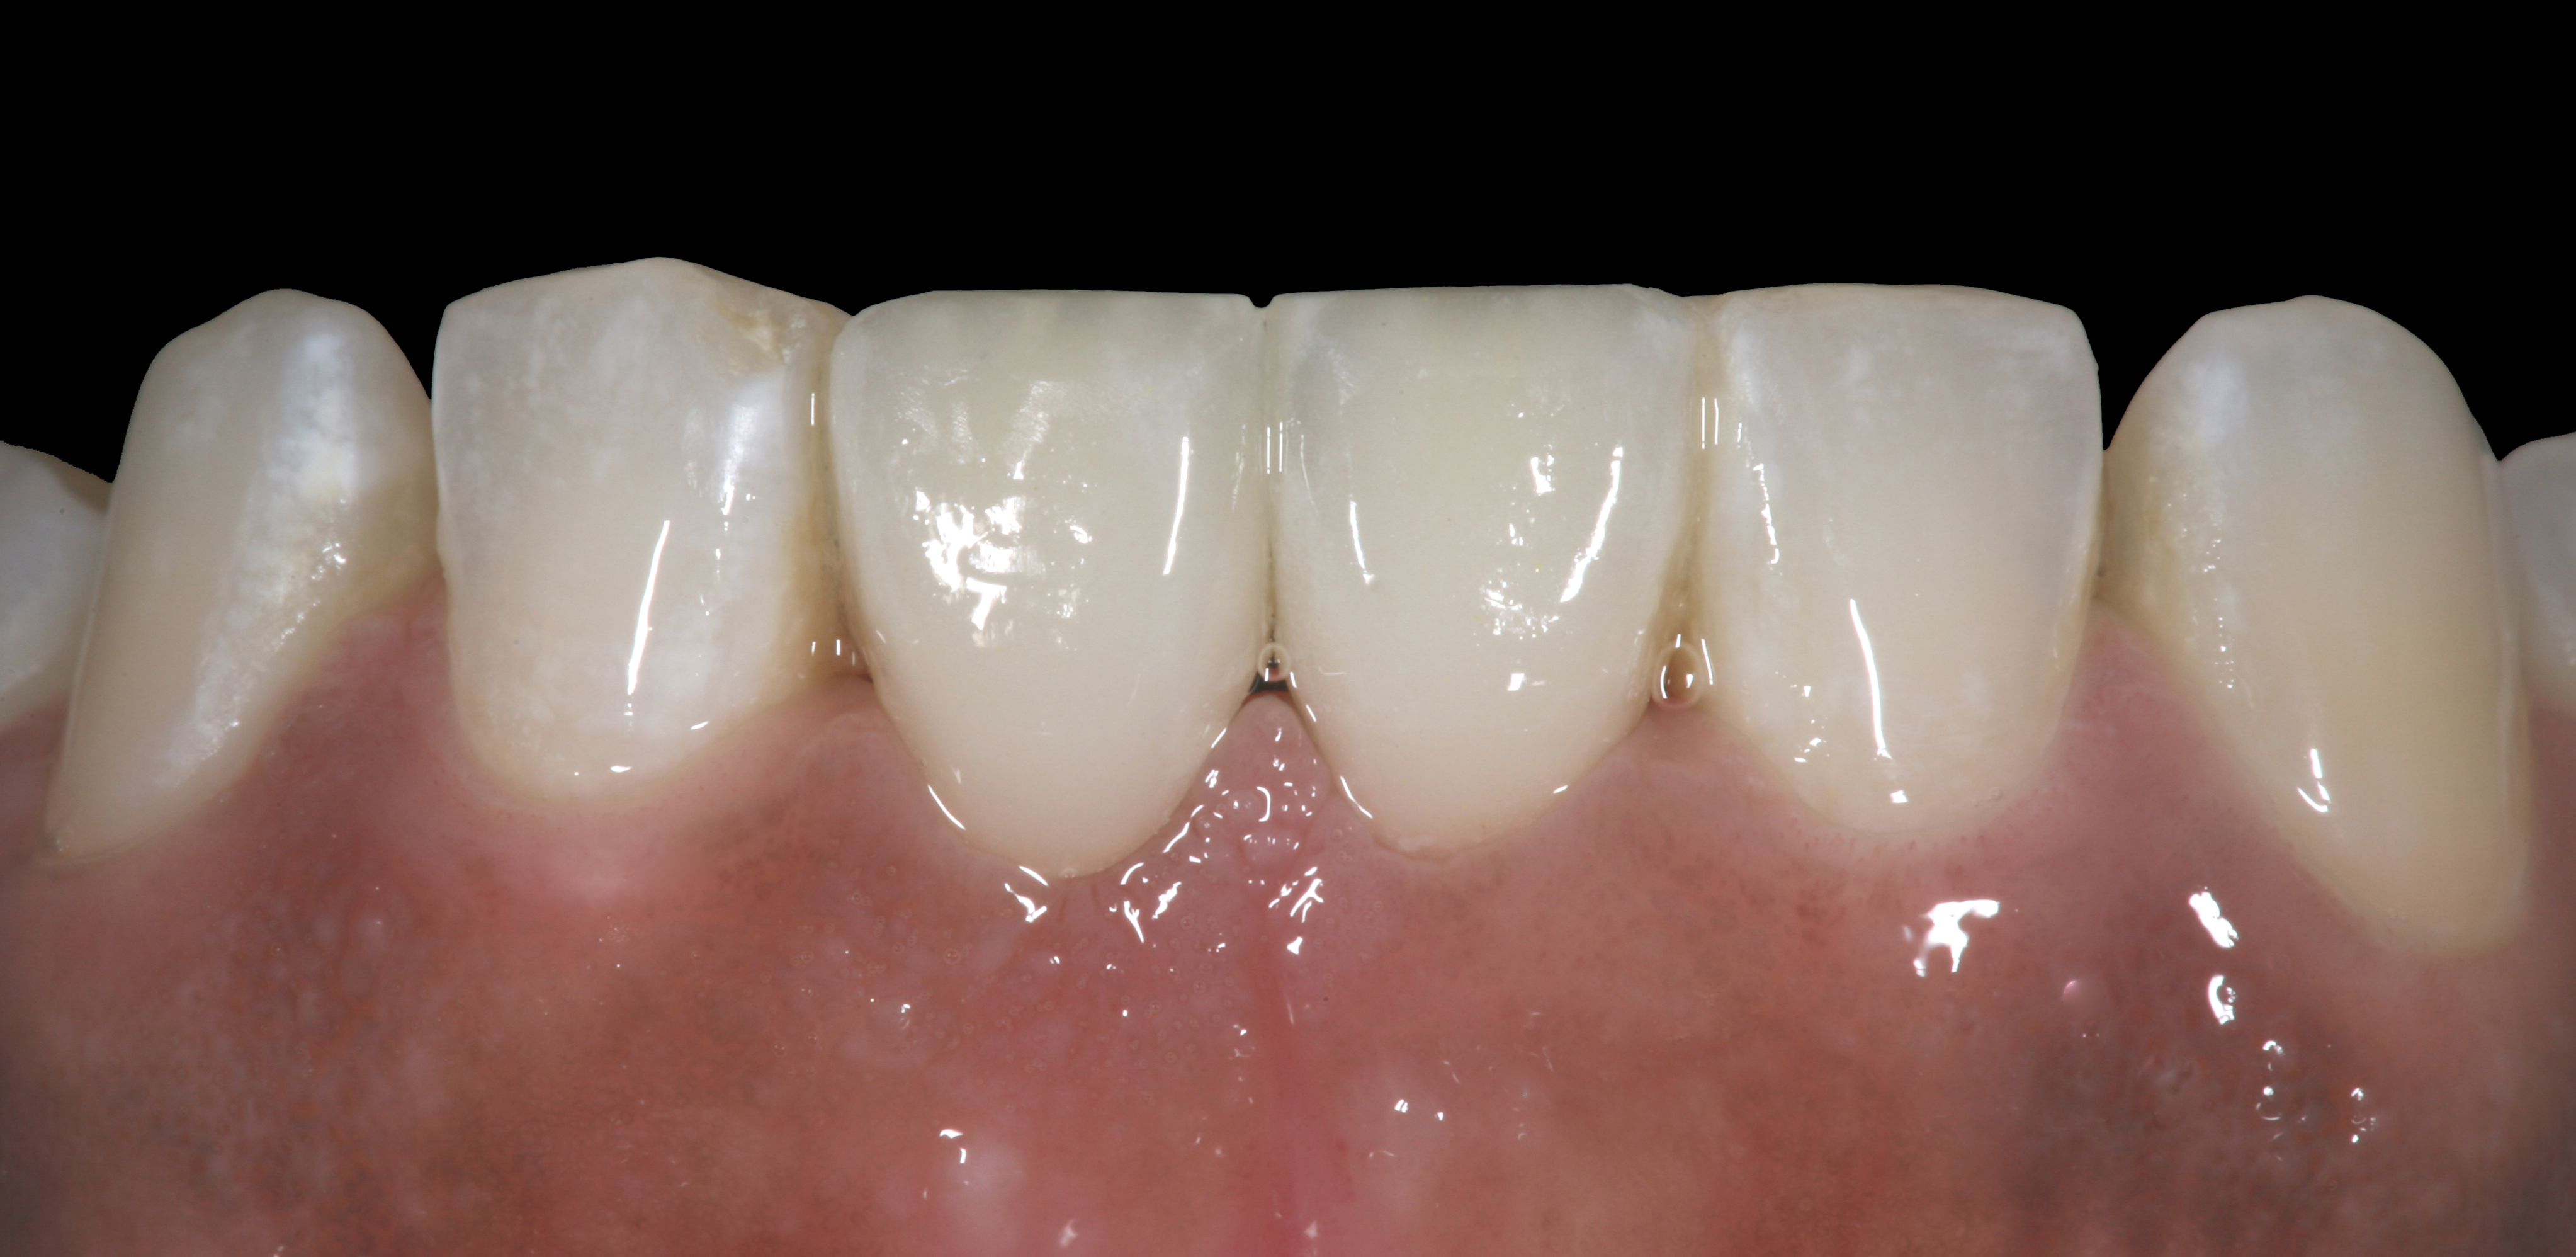

High-strength ceramic materials can be used in select cases to fabricate resin-bonded bridges to replace missing teeth as an alternative to removable prostheses or more invasive procedures such as conventional bridges or dental implants. The two missing lower central incisors (Figure 6) were replaced with two zirconia-based resin-bonded bridges (Figure 7). The single-retainer wing design has shown more than 94% clinical success after 10 years, which is significantly higher than the conventional two-retainer design (67.3% success).6 Proper bonding, however, is key for success and employs an air-particle abrasion step (Figure 8) followed by the application of a special ceramic primer (Figure 9). Figure 10 through Figure 12 demonstrate the clinical outcome.

Figure 6

Figure 7

Postoperative situation: left lateral view.

Figure 11

Postoperative situation: right lateral view.

Figure 12